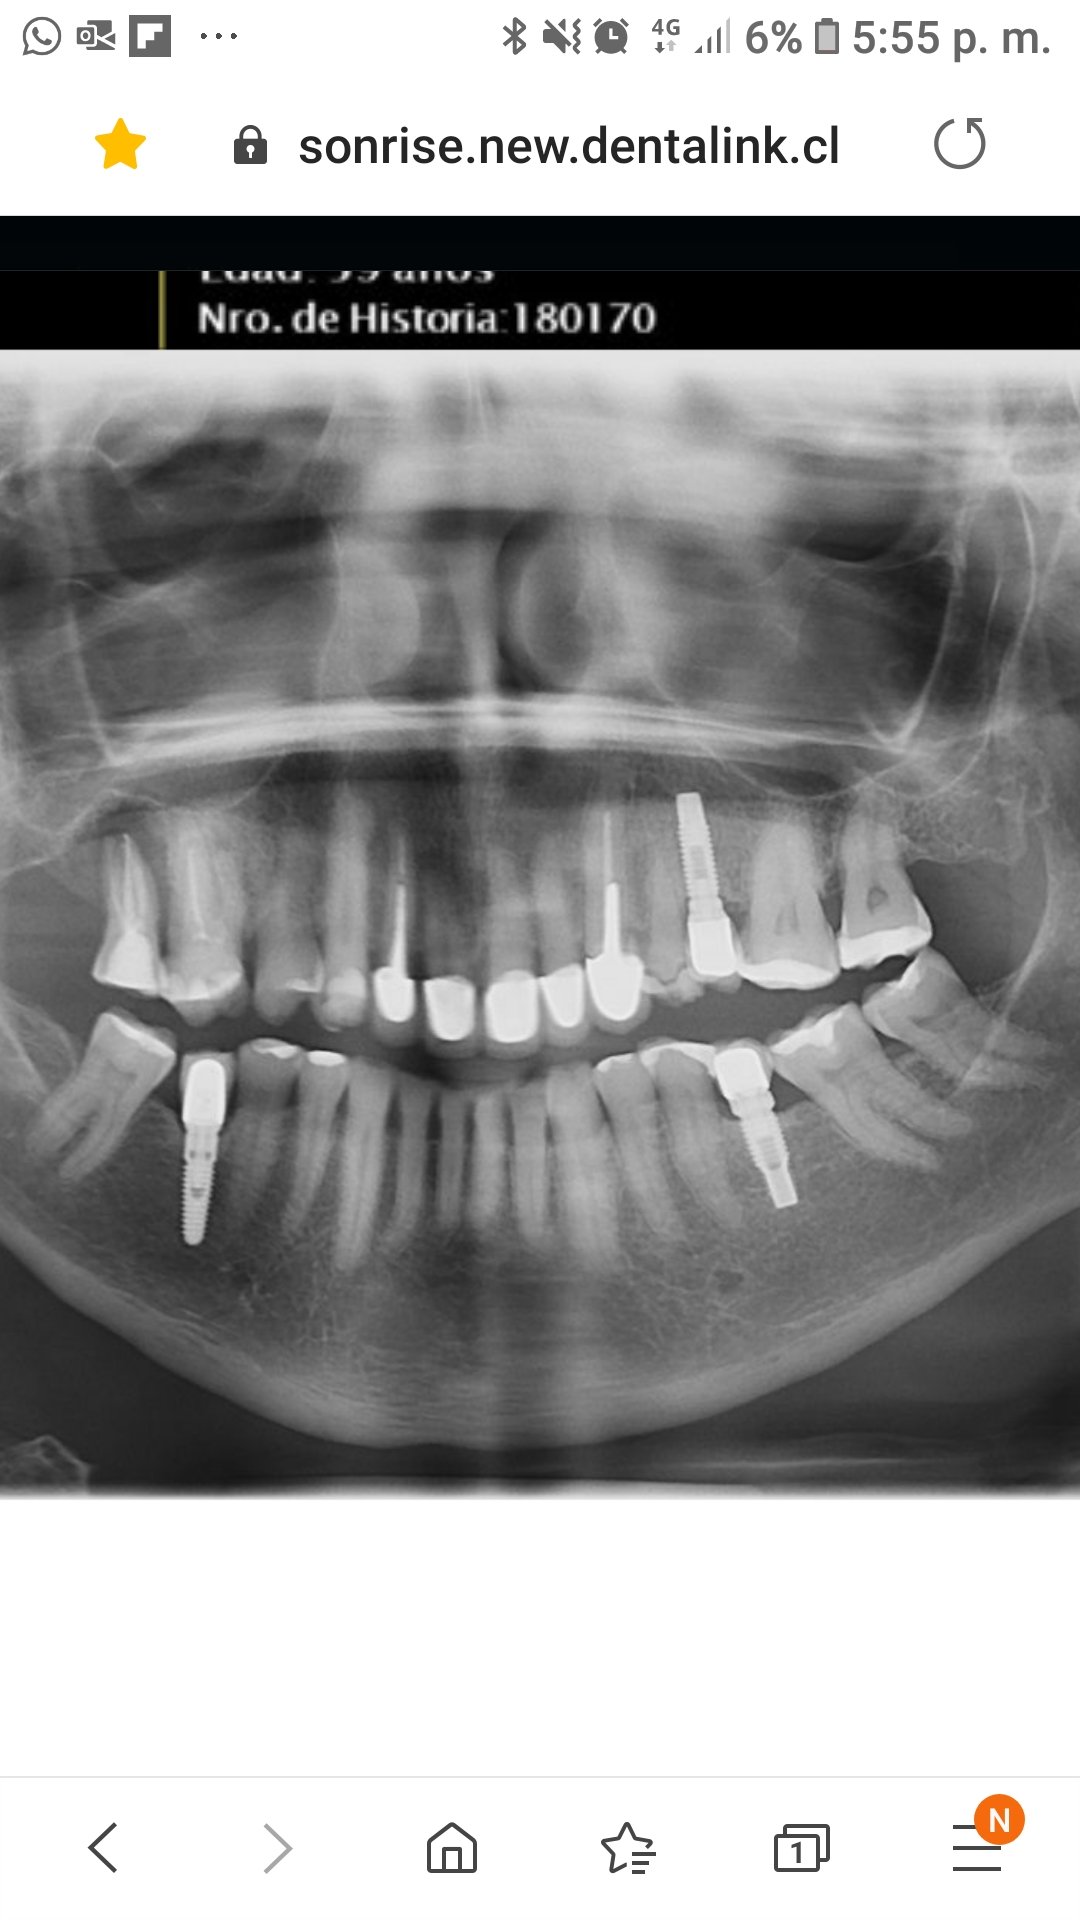

NECESITO SABER QUE IMPLANTES LLEVA.

se necesita rehacer la barra que lleva esos implantes. Lo que se observa desadaptado, es que la prótesis se confecciono con una entrada redonda, y asienta "sobre el hexágono externo" [...]

son de conexión externa pero desconozco qué marca y con qué serían compatibles para tomar medidas y hacer protesis

Implantes de conexión externa cuya marca desconozco. Necesito los superiores para terminar de rehabilitar el caso. Muchas gracias